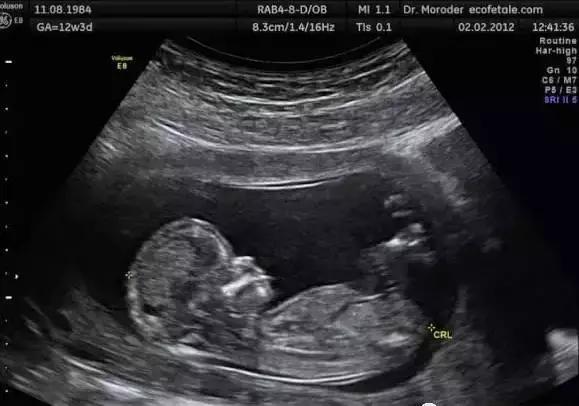

这名法国宝宝似乎太过好动,竟然在胎动的过程中一脚踢破妈妈的子宫,超声检查影像出来时,当场震惊了医师和母亲本人。

生命力惊人的小宝宝在妈妈的肚子里面不断的表现出惊人的活泼,没想到在妈妈某次产检时竟发现小脚丫已经踢破子宫,但因为孕妇没有任何不适,所以一直都没有发现。

该名妈妈的磁共振扫描(MRI)照片可以看到,箭头所指之处就是宝宝的双脚,而子宫壁处在怀孕初期已有2.5cm大的撕裂,使得部分装着发育中宝宝的羊膜囊露出子宫,宝宝也因为胎动刚好把脚伸出去,造成惊人的景象。